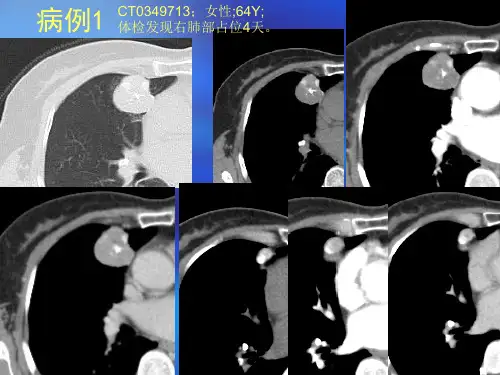

2015.01临床经验118<<下转119页肺错构瘤(Pulmoanry hamartomartoma )是肺部最常见的良性肿瘤,常认为是一种肺组织先天异常支气管构成的肿瘤样病变,现认为它是一种起源于支气管的未分化间质细胞良性肿瘤,需要与其它孤立性肺结节或肿块鉴别。

1 资料与方法1.1 一般资料收集我院1998年至2012年经手术或穿刺病理证实为肺错构瘤的患者23例,术前均行胸部CT 检查。

男17例,女6例,年龄28-71岁,平均年龄为48.5岁。

无临床症状20例(87%),有咳嗽、胸闷等轻微症状2例(9%),有咳嗽、胸痛及痰中带血丝1例(4%)。

1.2 检查方法使用美国GE-Hispeed Nxzisystems 螺旋CT 扫描机,扫面范围胸廓入口至膈肌。

通常行常规平扫(层厚/间距5~10mm )发现病灶后,局部改用薄层高分辨平扫,取结节最大层面测量CT 值,增强后CT 值与该兴趣区平扫CT 值之差(避开钙化区)即为该病灶强化程度。

肺软骨瘤样错构瘤的CT表现及鉴别诊断摘要】目的:通过自2011~2014年统计我院肺软骨瘤样错构瘤病例,分析其 CT表现及鉴别诊断。

方法:对108例行 CT检查并经手术病理证实的肺软骨瘤样错构瘤进行回顾性分析。

结果:中央型 6 例,周围型102例,平均直径 1.3cm,形态均较规则,仅12例内部可见明确钙化灶和脂肪成分。

结论:肺软骨瘤样错构瘤的 CT 表现有一定特征性,多位于胸膜下,形态规则,边界清晰,密度较同样大小的肺癌和炎性结节要高,并且均匀多见,增强后无强化或轻度强化。